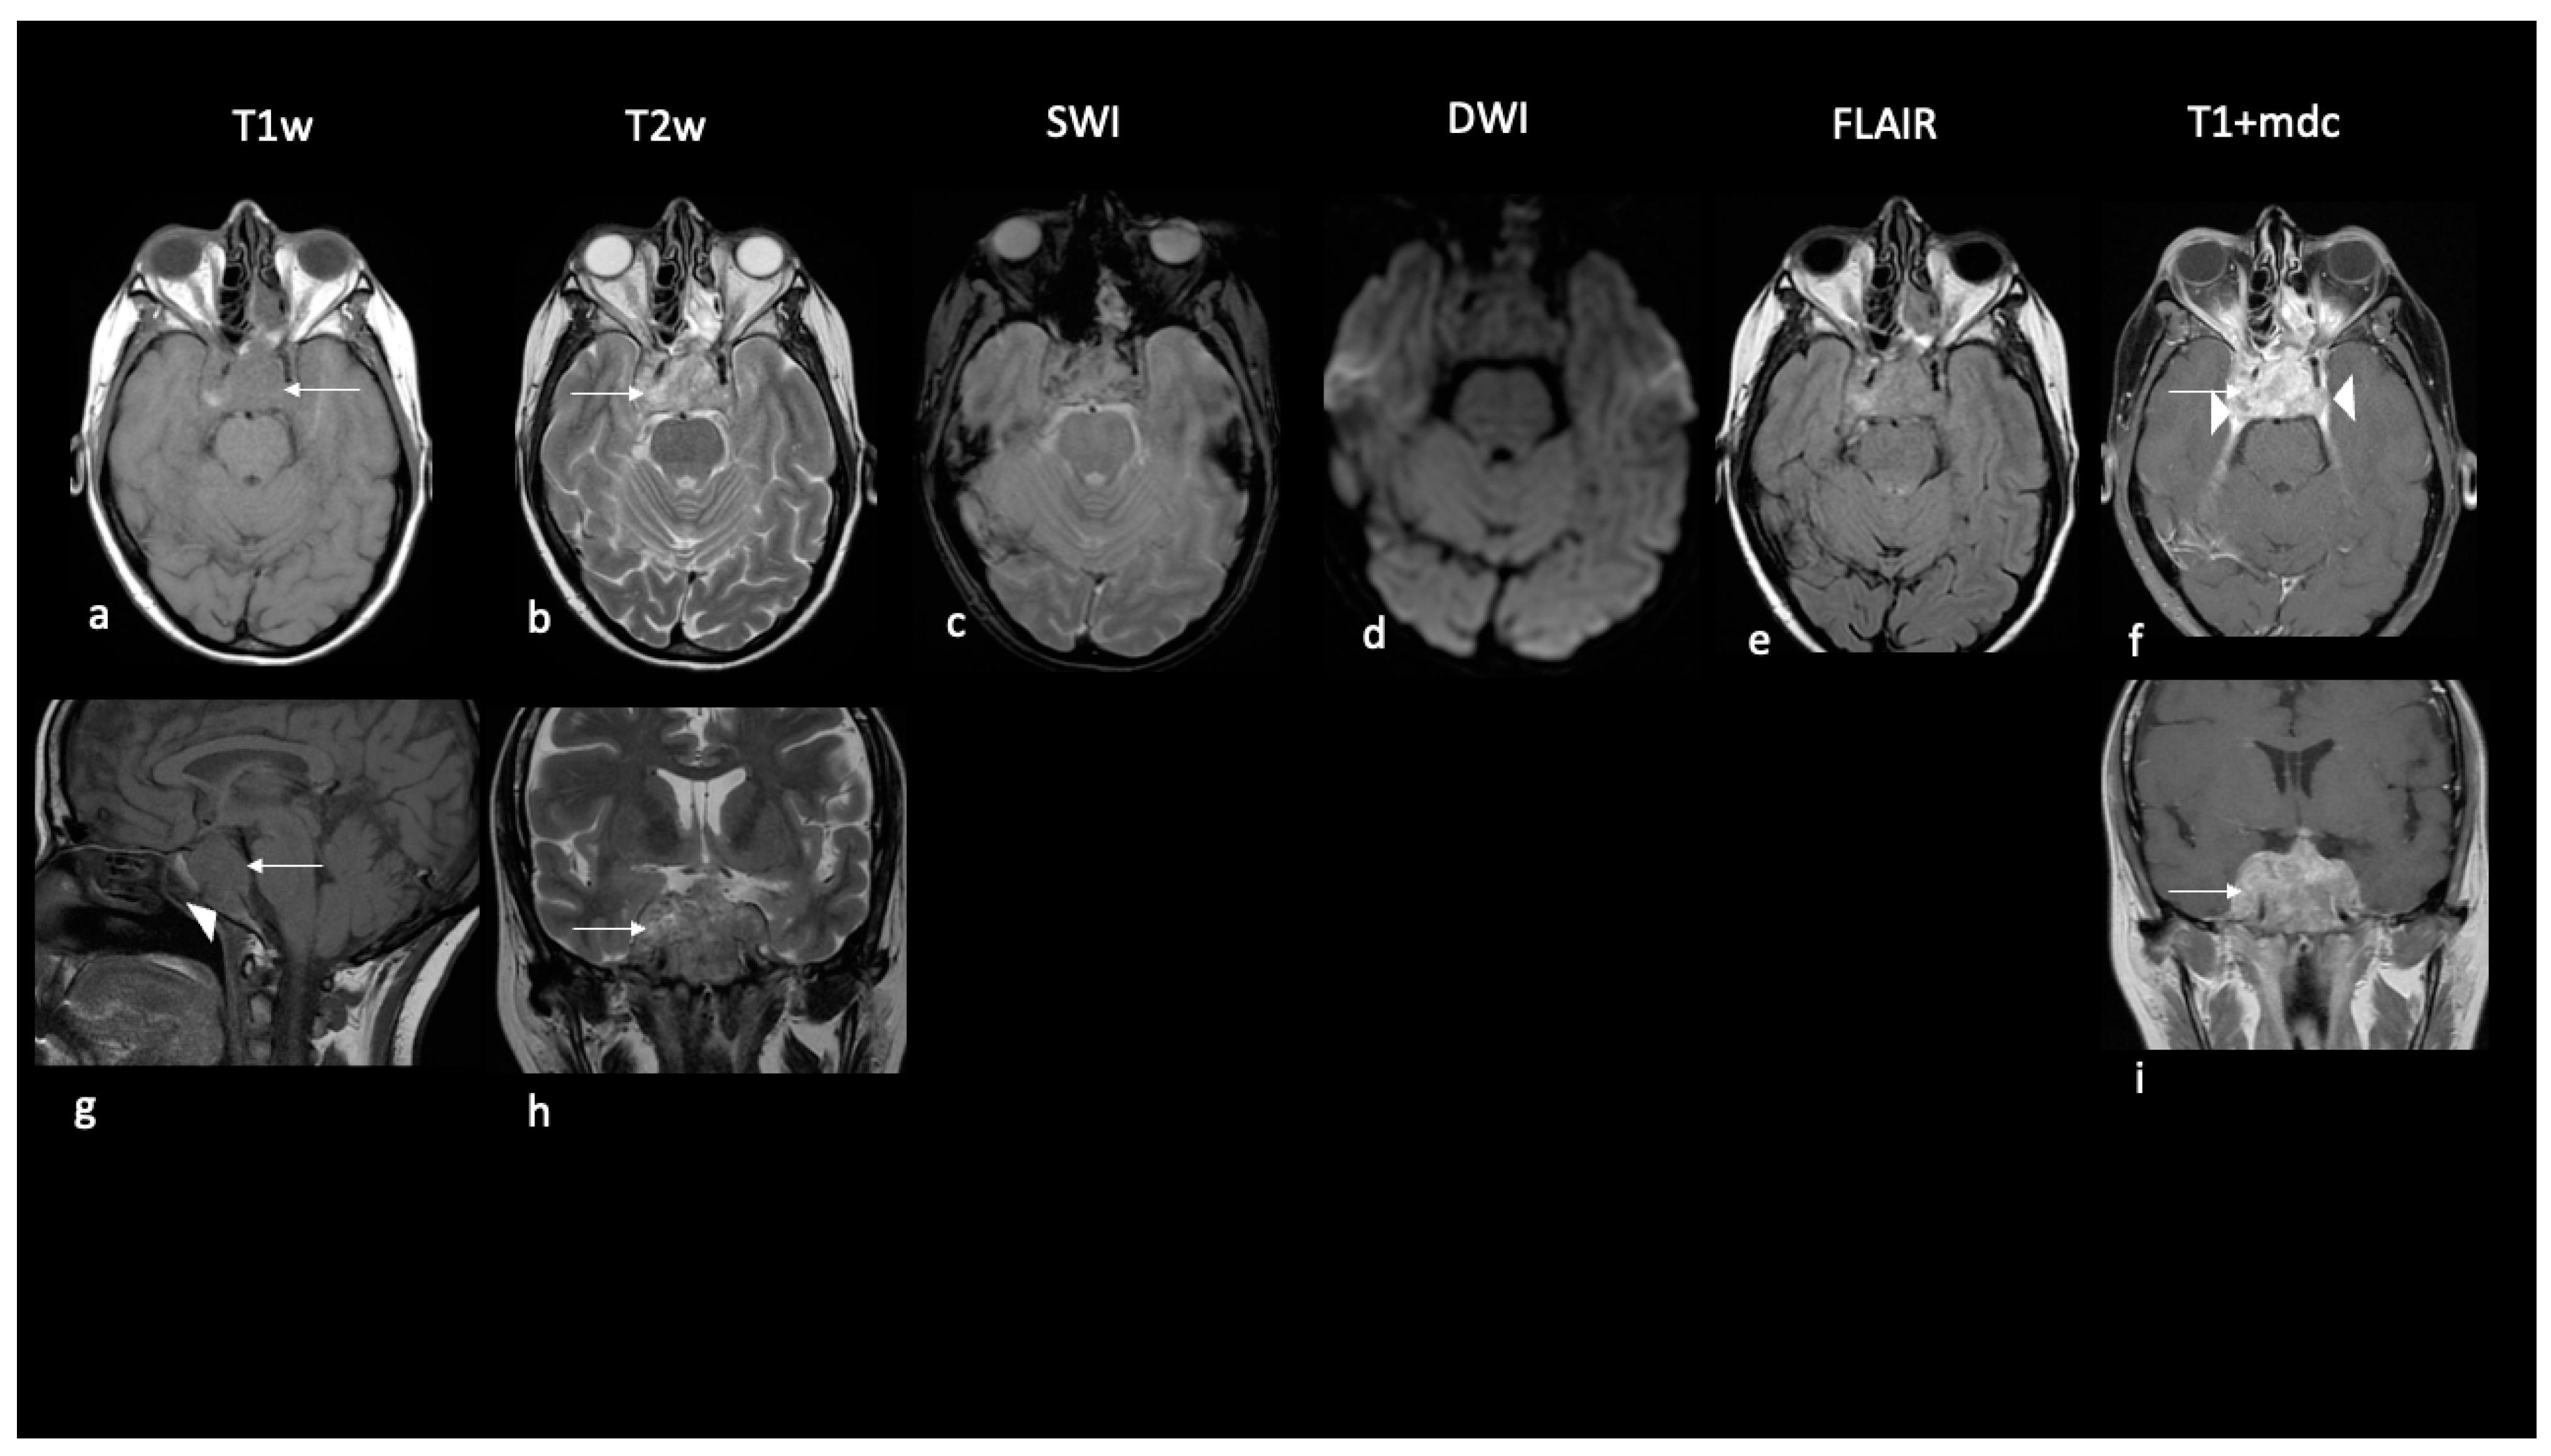

The adult-onset sellar-suprasellar tumor was predominantly solid and homogeneous and did not show restricted signal on DWI or edema but showed destruction of the clivus bone (Table 2, Figure 3).

Figure 3.

Imaging findings of sellar ATRT in an adult. Ax T1w (a,g); Ax T2w (b,h); SWI (c); Ax DWI (d); Ax FLAIR (e); Ax T1w+mdc (f,i). A local aggressive mass centered in the sellar region in an adult of 43 years. The mass is prevalently solid, hypointense in T1w (arrows in (a,g)) and hyperintense in T2w (arrows in (b,h)) to gray matter with marked enhancement (arrow in (f,i)) invading cavernous sinus (arrowheads in (f)) and clivus (arrowhead in (g)). Decreased diffusivity and interstitial edema are absent.